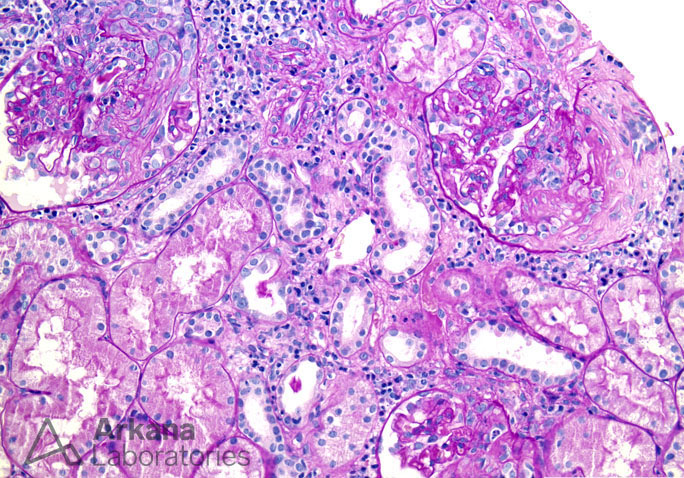

Previous Image Next Image Fibrocellular Crescent Formation and Interstitial Inflammation in Lupus Nephritis on PAS Like Loading...